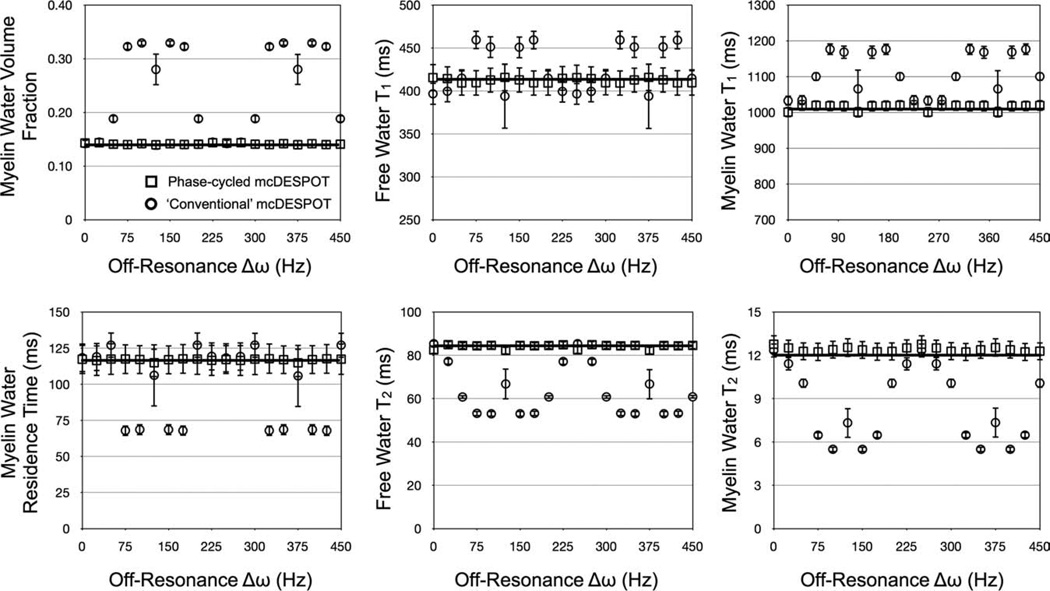

Results of the RF phase-cycling simulations are shown in Figs. 7 and 8, which show corrected and uncorrected T1,M, T1,F, T2,M, T2,F, fM, and tM estimates over a range of myelin water volume fraction and off-resonance values. The sensitivity of mcDESPOT to off-resonance is visually demonstrated in Figs. 7 and 8. The uncorrected estimates show significant deviation from the true theoretical values at even subtle δω. The inclusion of off-resonance modeling significantly improves the accuracy of the derived parameter estimates, with less than 5% absolute error observed in each of the parameters across the investigated myelin fraction and off-resonance values.

FIG. 7.

Simulation results exploring B0 and off-resonance affects on derived mcDESPOT parameters. Uncorrected estimates (circles markers) show significant deviation from theoretical truth (denoted by the line). This error is substantially reduced with the inclusion of off-resonance modeling (square markers), which are approximately independent of off-resonance value.

FIG. 8.

Simulation results of the accuracy and precision of off-resonance corrected myelin water volume fraction estimates. Error in the derived estimates was less than 5%.